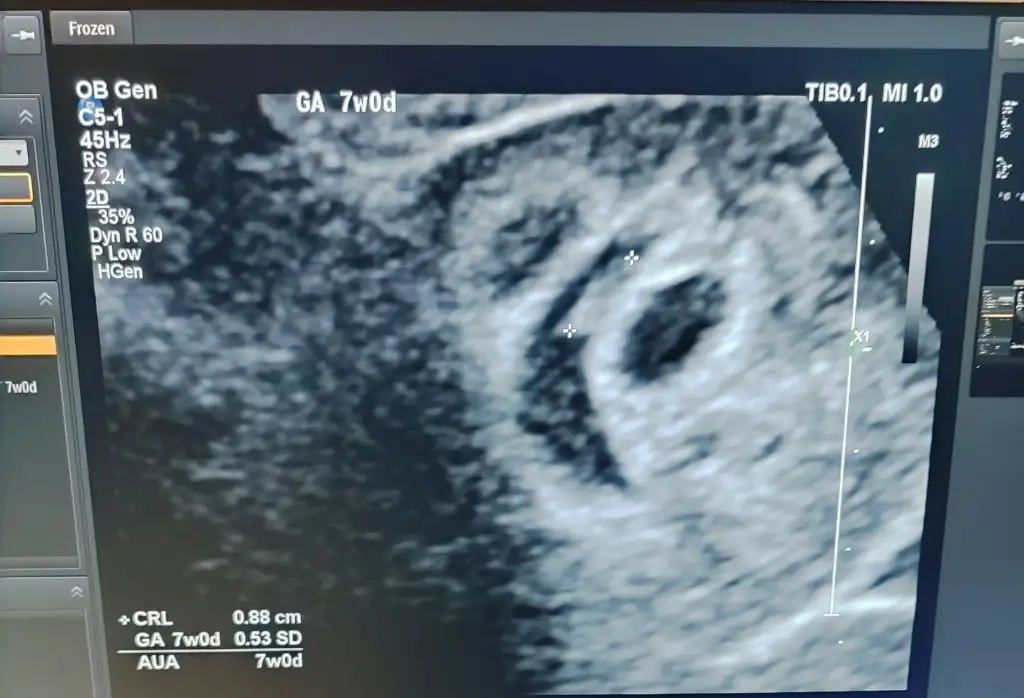

1 embriyo transferi 3 kese

7 haftalık olan kalp atışını duydunuz mu

Evet

Kanama demedi ikiside kese olarak görüyorlar

Hmm bana da öyle dediler ama imkansız öyle olması, gelişiyor içinde bebek oluşursa kese denilebilir ama şuan kanama alanı gibi görünüyor aynı durumu bnde yaşadım hemde düzgün görünümlüydü 2 farklı doktora gittim ikisi de anlamadi kese gibi dedi ama malesef benim gebelik kesesi boş gebelik oldu, sizin farklı olabilir bilemem ama kese olmasi zor bi ihtimal

Bilemcm artık belli olur 10 gün sonra hayırlısı olsun